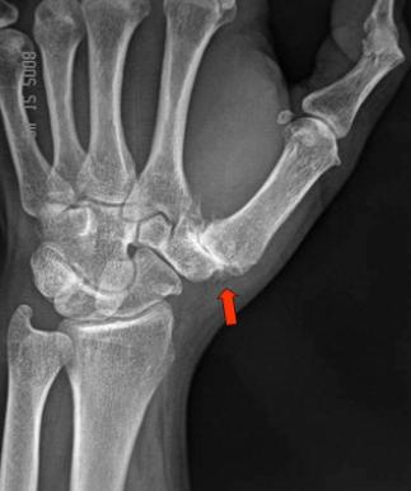

Gamekeeper Thumb/ Ligament Tear

Pathophysiology:

Traumatic rupture of UCL of thumb

Can be acute, single injury or repetitive trauma that finally ruptures

Tests: x-rays and MRI to confirm injury and look for avulsion fx

1. scaphoid Fx 2. buckle/torus fx 3. ulnar styloid fx